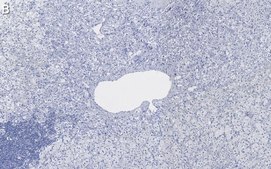

Immunohistochemistry (Paraffin) Analysis: A 1:1,000 dilution from a representative lot detected Dopamine β Hydroxylase in human adrenal gland tissue sections.